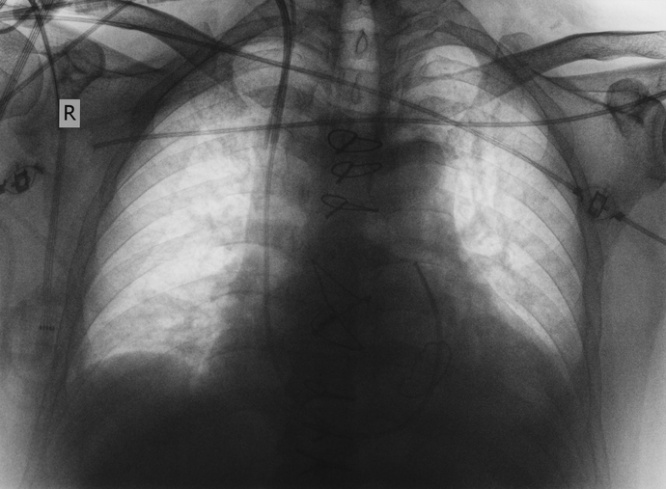

やっとのことでレントゲンを撮ってみたところ、カテーテルは肩関節のところまで入ってい

るのがわかった。最終的に60センチ押し込んで、ついに目的地である心臓の心室まで到達させた。

エバースヴァルデ病院の臨床医のヘッドは、最初、フォルスマンのこの実験に青くなったが、レントゲン写真を見せられると、喝采を送った。